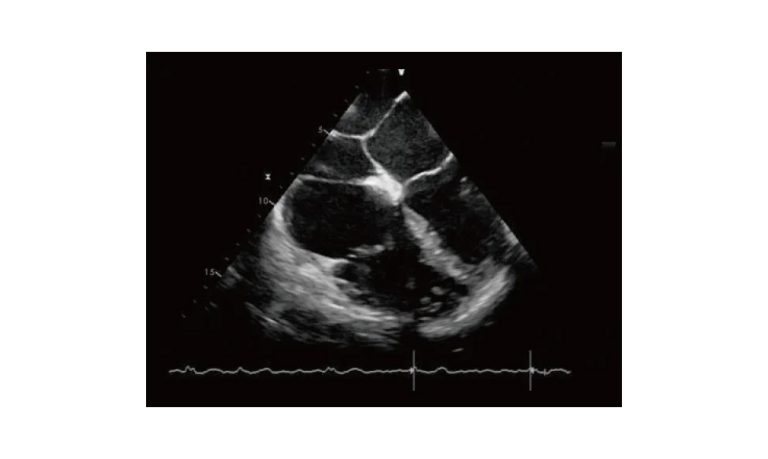

Esaote MyLab Sigma; So Fast, So Easy

Esaote’s new MyLab™SigmaVET is the smart, portable solution that allows use of an ultrasound whenever a quick and complete diagnosis is required.

- Dedicated VET software and probes

- Windows® 10

- Quick start-up

- Highly responsive capacitive touchscreen

- Pivoting 15.6” monitor2 probes connectors

- Easy to carry